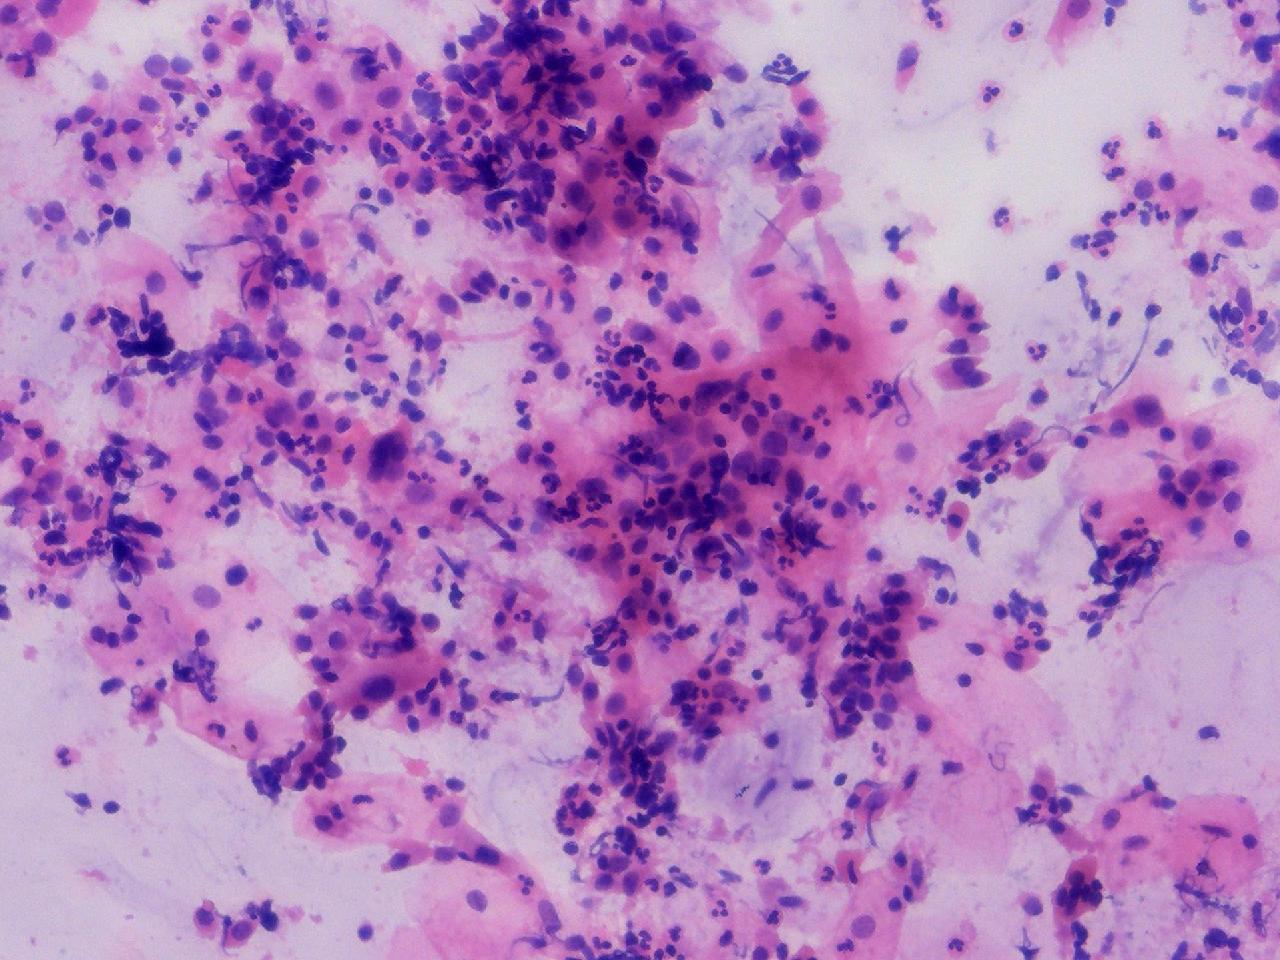

可见较多腺细胞。请教诊断。

性别

女

年龄

55岁

一般病史

绝经2年余,阴道淡血水3月余,子宫肌瘤10余年,HPV不详。

标本类型

妇科TCT

制片方法

离心后,沉降式制片

染色方法

NILM